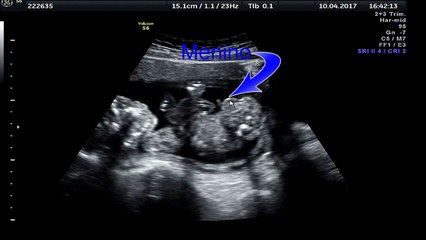

Você consegue imaginar ver o rostinho do bebê ainda na barriga como se ele já estivesse nos seus braços? Parece impossível, mas isso já é realidade! Graças ao avanço da tecnologia, novos ultrassons em 8K com inteligência artificial (IA) estão transformando a gestação em uma experiência realista.br br A inovação ganhou destaque com clínicas especializadas como a Sweet 3D Baby, localizada na Califórnia (EUA), que vem encantando pais com imagens ultrarrealistas dos bebês ainda no útero.